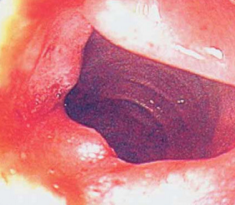

Zenker Diverticulum

<div id="article-content-body"><p><a href="http://imaging.cmpmedica.com/consultantlive/images/articles/2006/12012006/0612ConPCZenker.jpg"><img...